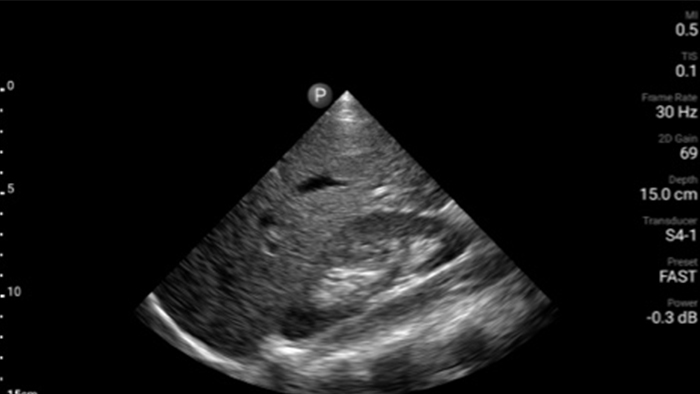

Early detection can help keep conditions from becoming critical

Congestive heart failure is a growing issue today. Discovering it earlier with in-office ultrasound can greatly improve survival rates.

Cardiac tamponade masquerades as abdominal pain

Assessment of left ventricular function